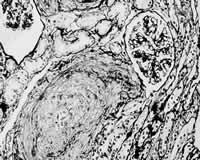

腎小動脈栓塞診斷檢查